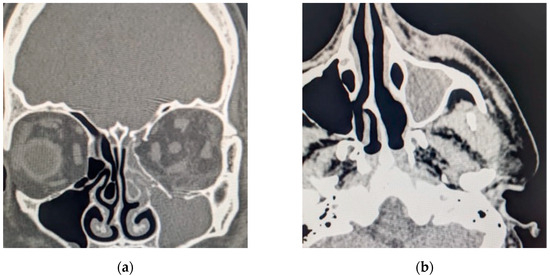

The head CT revealed a large left-sided orbital abscess of 25 × 14 mm, a left preseptal eyelid abscess with a thickness of 9 mm, left maxillary sinus opacification, posterior globe tenting, and retromaxillary soft tissue swelling with a thickness of 7 mm with extension in the orbit via the inferior orbital (Figure 10).

Figure 10. Computed tomography scan section displaying (a) coronal section with maxillary sinus opacification and orbital abscess; (b) axial section with maxillary sinus opacification.